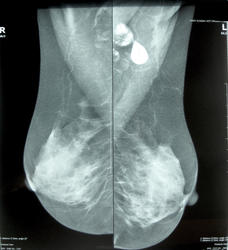

59 лет. Жалоб нет. Находка при профилактической маммографие. Ни чем особенным не болела.

фиброзно-кистозная мастопатия, Вас смущают шарики??? плотность у них прям стремится к металлической

В железе чисто, в проекции большой грудной мышцы какая-то мегахрень)

Не могут быть следы от дезодоранта?Там содержится свинец.

Свинец от дезодоранта обычно выглядит по другому: в виде россыпи мелких точечных интенсивных теней. А здесь в таком случае должна быть 2 см капля свинца.

А вот еще результаты УЗИ: слева в аксиллярной области эхонегативные образование, полностью поглощающее уз-сигнал, образующее за собой акустическую тень. Расположено в подкожно-жировой клетчатке, прилежит к коже.

Рядом - подозрительный л/узел, в воротах которого несколько гипоэхогенных образований.

Какие еще будут мнения о природе кальцината?

справа в верхне-наружном кв. возможно фиброаденома, а в аксилярной  области лимфоузлы с обызвествлением.